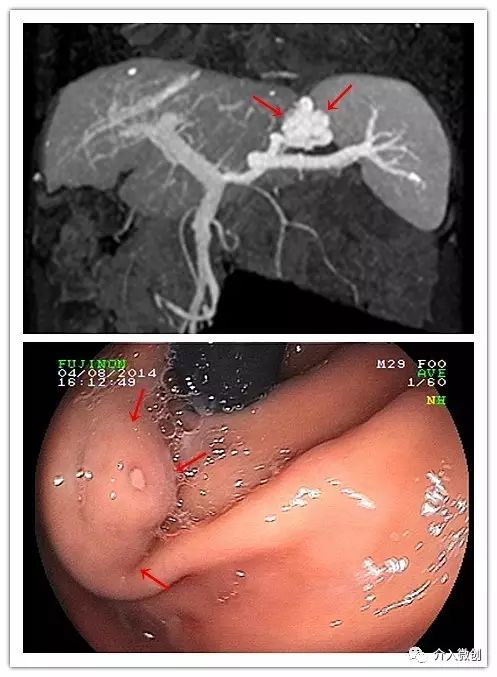

- CTA显示孤立性胃底静脉曲张,胃肾分流;电子胃镜示胃底部静脉曲张。